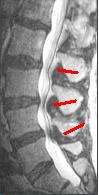

MRI

The MRI has become the most frequently used study to diagnose spinal stenosis. The MRI uses electromagnetic signals to produce images of the spine. MRIs are helpful because they show more structures, including nerves, muscles, and ligaments, than seen on x-rays or CT scans. MRIs are helpful at showing exactly what is causing spinal nerve compression.[15]